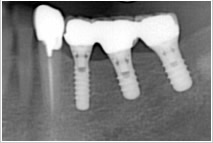

写真の患者様は、向かって左の奥から3番目に1本だけ、インプラントが入っています。

ほとんどの歯がとても健康な状態で残っていましたので、歯を削ってブリッジにすることは抵抗がありました。

そこで、インプラント手術を行い、周囲の歯を傷つけず健康な状態で残しました。

インプラントは周りの歯に負担をかけない仕組みになっているので、欠損部位にインプラントを応用することで歯は守られ、左右でしっかりと噛めるようになられました。